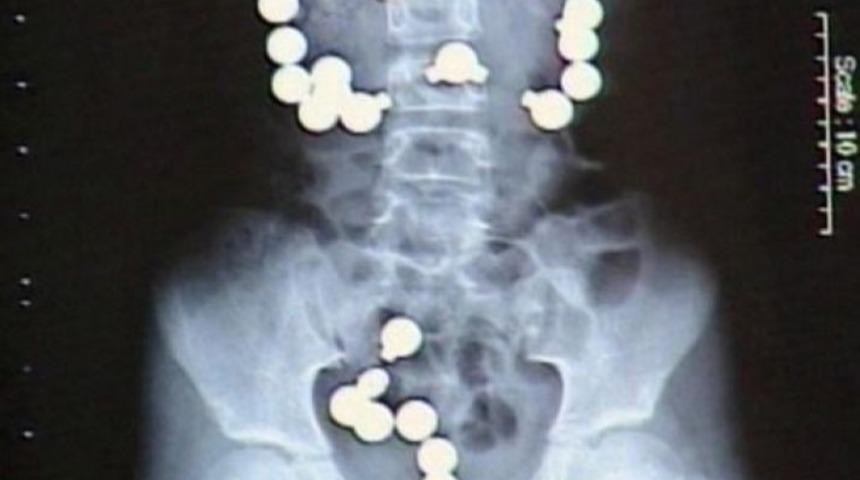

Haley Lens adlı 8 yaşındaki küçük kız, mide ağrılarından şikayet edince ailesi onu doktora götürür. Röntgen filminin sonucunda 30 adet metal magnet yuttuğu anlaşılır.

Top şeklindeki 30 adet metal magneti neden yuttuğunu soran doktorlara, kızın cevabı şöyle olur; ''Şekere benziyorlardı...''